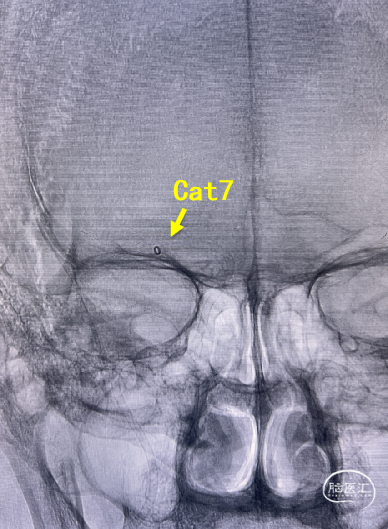

BADDASS技术下支架取出长条血栓,3D-DSA可见眼动脉下方重度狭窄,CAT 7在张力下的上行切割狭窄处,导致小夹层产生。

术后RICA造影 :mTICI 3级。